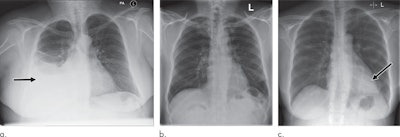

Based on its analysis of the reports, the NLP system was able to prioritize each image as critical, urgent, nonurgent, or normal. Using these image labels, the CNNs were trained to predict the clinical priority of the x-ray images based only on their appearance. Predictions were averaged from the two different CNNs, which operated at two different spatial resolutions, to arrive at the final prediction for the system.

In testing, the system was able to separate normal from abnormal radiographs with 71% sensitivity, 95% specificity, 73% positive predictive value, and 99% negative predictive value. In terms of determining priority level, the AI system achieved 65% sensitivity, 94% specificity, 61% positive predictive value, and 99% negative predictive value for identifying critical studies.